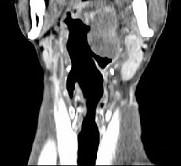

问题 男,67岁,口咽部异物感约8个月,伴口咽部疼痛,患者无明显发热.如图所示最可能的诊断为()

选项 A.扁桃体结核伴淋巴结转移 B.扁桃体脓肿伴淋巴结转移 C.扁桃体癌伴淋巴结转移 D.扁桃体淋巴瘤 E.下咽癌伴淋巴结转移

答案 C